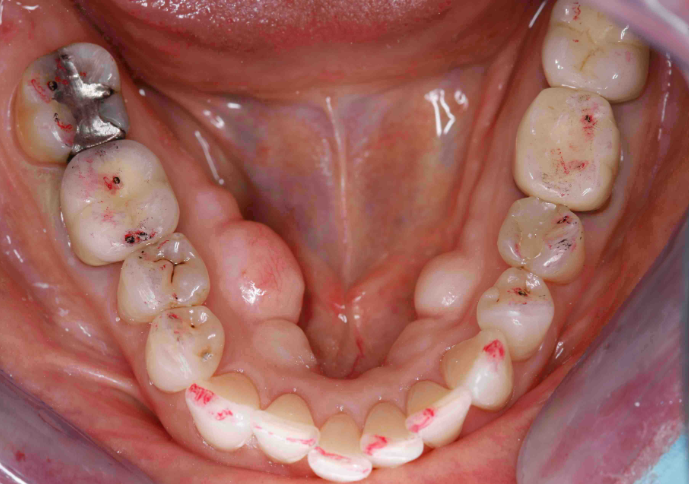

B. Case Studies & Clinical Applications

- Case Study 1: TENS-guided occlusion calibration in a full-arch zirconia restoration.

- Case Study 2: EMG-driven adjustments for implant-supported prostheses.

- Outcomes: Enhanced bite stability, reduced muscle strain, and improved patient comfort.